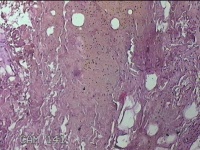

左侧会阴部皮下结节

性别

女

年龄

45岁

临床诊断

皮下结节

一般病史

发现左侧会阴部皮下结节2年余,伴近日局部隐痛不适。

标本名称

大体所见

灰白暗红色结节0.8x0.7x0.3cm一个,表面糜烂。

图3